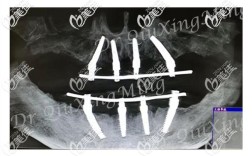

设备与材料支持

在硬件设备方面,杭州口腔医院配备了全套数字化种植系统,包括CBCT(锥形束CT)、3D口扫仪、数字化种植导板设计软件等,可实现术前精准模拟种植位置、角度及深度,减少手术创伤,提高种植体与骨组织的贴合度,材料选择上,医院提供多种国际主流种植体品牌,如瑞士Straumann(士卓曼)、瑞典Nobel Biocare(诺贝尔)、德国Ankylos(安格斯)、韩国Osstem(奥齿泰)、Dentium(登腾)等,覆盖不同预算和骨质需求的患者,种植体材质多为生物相容性良好的钛及钛合金,确保长期稳定性。